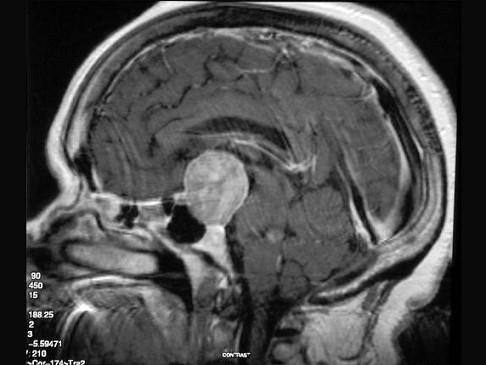

垂体腺瘤(如图所示)首选的治疗方法为()A.溴隐亭治疗B.放射治疗C.化学治疗D.手术治疗E.伽玛刀治疗

问题 垂体腺瘤(如图所示)首选的治疗方法为()

选项 A.溴隐亭治疗 B.放射治疗 C.化学治疗 D.手术治疗 E.伽玛刀治疗

答案 D